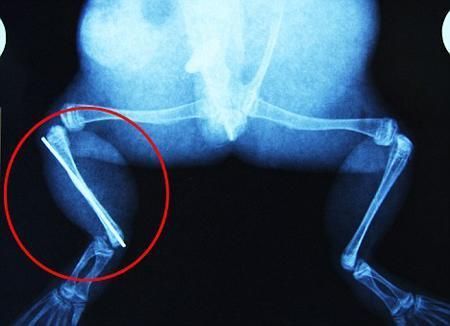

環(huán)球網(wǎng)4月2日?qǐng)?bào)道 據(jù)《每日郵報(bào)》報(bào)道,上個(gè)月,南非大牛蛙布魯萊的右小腿被鄰居家的一只狗咬到,導(dǎo)致粉碎性骨折,現(xiàn)在經(jīng)過(guò)2個(gè)小時(shí)的手術(shù),它的斷腿已經(jīng)被接上,它也因此成為有史以來(lái)第一只通過(guò)外科手術(shù)用鋼針接上斷腿的青蛙。

野生生物專家安妮經(jīng)常為學(xué)校寫教材,她認(rèn)為這是人類第一次通過(guò)手術(shù)給一只青蛙接斷腿。在手術(shù)開(kāi)始階段,獸醫(yī)把少量給狗用的麻醉藥注入到這只青蛙體內(nèi),讓它失去知覺(jué)。然后他在布魯萊的斷腿上切開(kāi)一個(gè)小口,把一根小鋼針植入腿里。最后獸醫(yī)給它縫了9針,把切口縫合在一起。僅僅幾周后,布魯萊就能在安妮家附近活動(dòng)了。這只青蛙大約已有25歲,主要以嚙齒動(dòng)物、蛇和其他青蛙為食。布魯萊所屬的牛蛙種群正在不斷減小,目前只能在非洲南部的濕地里才能看到這種青蛙。

安妮有2個(gè)孩子,她已經(jīng)從事20多年兩棲動(dòng)物保護(hù)工作。她認(rèn)為鄰居家的狗狗在把布魯萊從地下刨出來(lái)的時(shí)候,它正在地下冬眠、她說(shuō):“世界上只有這個(gè)地區(qū)能看到這種牛蛙,這種青蛙現(xiàn)在變得越來(lái)越稀少。因?yàn)槲覐氖乱吧锉Wo(hù)工作,因此認(rèn)識(shí)很多兩棲動(dòng)物專家,但是以前他們誰(shuí)也沒(méi)見(jiàn)過(guò)這種事情?吹讲剪斎R越來(lái)越健康我非常開(kāi)心,F(xiàn)在還需要一段時(shí)間,它的金屬腿和它的骨骼才能融為一體,那時(shí)布魯萊會(huì)跟以前一樣健康。我們認(rèn)為這個(gè)過(guò)程需要幾周時(shí)間,但是一旦它完全康復(fù),我希望把它放歸大自然,讓它重新回到它最鐘愛(ài)的濕地里!